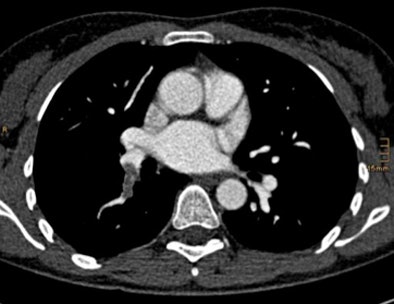

| Above, CTA showing an axial scan with an embolus at the right lower lobe. Below, corresponding coronal pulmonary blood volume map shows a perfusion defect of the right lower lobe. Images courtesy of Tobias de Zordo, MD, and Gudrun Feuchtner, MD. |

On DSCT images, seven patients with pulmonary emboli showed perfusion defects in the corresponding lung parenchyma. In one patient, a triangular perfusion defect was found without a corresponding pulmonary embolus. "We didn't have any additional perfusion defects; we don't know if it's artifact or something else -- the lung window couldn't find anything," he said.